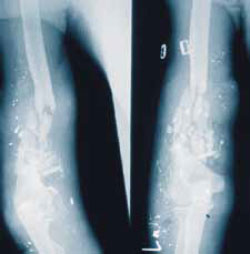

9. Металлические осколки: следует обратить внимание на разницу между неповрежденной пулей (M1) и разрушенной пулей (M2), как это показано на рисунке 6. Если сплошная металлическая оболочка пули разрушается и внутренний свинцовый сердечник разлетается в виде осколков, то это является показателем громадной нагрузки, приложенной к пуле, и большой передачи кинетической энергии на ткани (рисунок 7 и 8 3.35 и 10.5).

Рисунок 8. Тяжелый раздробленный перелом плечевой кости, образовавшийся после разрушения пули «свинцовый дождь»